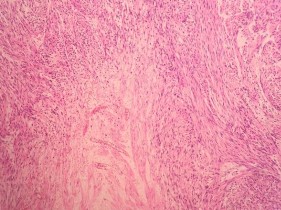

(Bệnh nhân: Triệu Tài V.)

HE x 100: Các tế bào u hình thoi, nhân bàu, bào tương hồng, sắp xếp thành bó | HE x 400: Không rõ màng nhân, giàu nhân chia. |

SMA: Dương tính mạnh bào tương | DESMIN: Dương tính bào tương |

CALDESMON: Dương tính với bào tương | DOG 1: Âm tính với tế bào u |